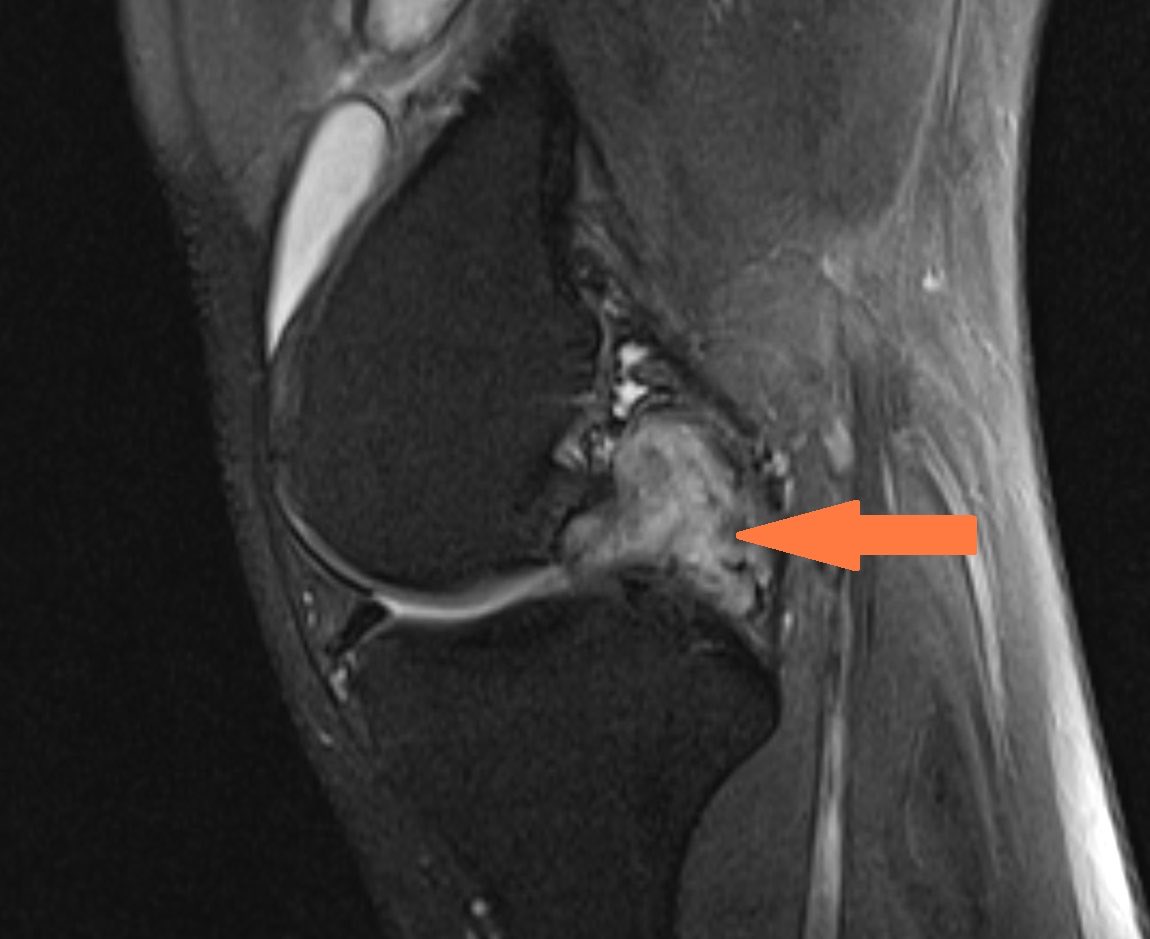

BREAKING: Utah Jazz star Jaren Jackson Jr. is likely to miss the remainder of the season to undergo surgery on his left knee to ensure his longterm health after a localized PVNS growth was discovered post trade, league sources tell me.